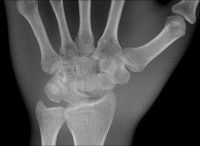

The multifunctional panels can be used in a number of clinical settings, including intensive care for bedside examinations, while portable DR detectors have created new applications in trauma, pediatric, and orthopedic settings.

The industry's first detector featuring wireless image transmission, the DRX-1 from Carestream, was introduced in 2009 at the University Hospital in Frankfurt and subjected to a series of studies by Vogl's group against conventional computed radiography (CR) systems for both image quality and workflow efficiency. As a result of the positive findings from the studies for superior image quality and dose efficiency, the DRX-1 detector is now used as part of routine protocol.

Identical in size to a standard CR cassette, the detector can be inserted into an existing wall stand or table Bucky and used in combination with existing x-ray generators from a number of original equipment manufacturers, presenting an attractive option for modest-budget facilities. The flexibility of the portable detector provides great advantages in time-critical environments where an x-ray image can now be captured and viewed in less than six seconds, he explained.